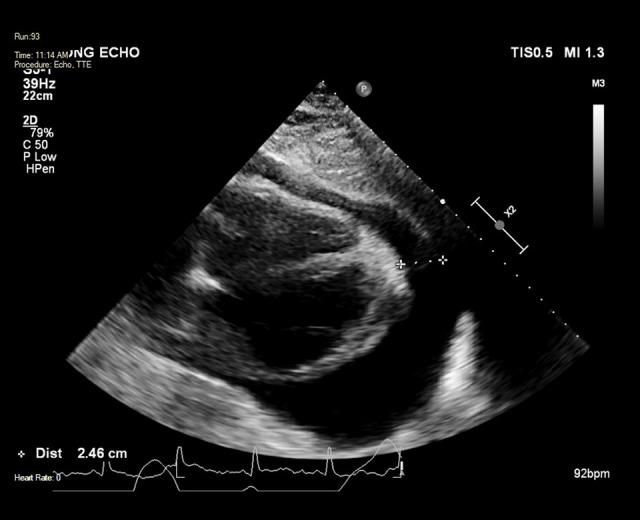

心包炎是系统性红斑狼疮(SLE)的常见并发症。然而,大量心包积液引起的心包填塞是一种罕见的后遗症。SLE患者发生心包填塞的危险因素包括女性、血清补体降低和诊断时抗核小体抗体阳性。心包填塞的治疗方案,如心包穿刺和心包开窗,都是针对个体量身定制的,并且缺乏关于何时进行侵入性干预的明确指南。病例报告:我们报告一例38岁女性SLE加重合并心包填塞,伴有发热、呼吸困难和胸膜炎性胸痛。胸片显示大量左侧胸腔积液掩盖了增宽的纵隔,怀疑为心包积液。在药物治疗试验后,患者出现了新的心房颤动、低血压和心动过速,并进行了心包穿刺,随后在接下来的24小时内抽出了1.6升心包液。采用高剂量脉冲皮质类固醇和环磷酰胺治疗,疾病得到控制,积液无复发。结论:这似乎是文献中描述的SLE患者心包引流量最大的一例。心包填塞可发生在SLE病程的任何阶段。大量胸腔积液可模仿心包积液的症状,使诊断具有挑战性。采用侵入性和药物治疗相结合的方法可以达到最终的治疗效果。心包填塞发生的危险因素应在SLE恶化的早期识别,以确保及时治疗并避免进一步的并发症。

BACKGROUND Pericarditis is a frequently encountered complication of systemic lupus erythematosus (SLE). However, cardiac tamponade resulting from massive pericardial effusion is a rare sequela. Risk factors for cardiac tamponade in SLE include female sex, reduced serum complement, and positive anti-nucleosome antibody at diagnosis. Management options for cardiac tamponade, such as pericardiocentesis and pericardial window, are tailored to the individual, and clear guidelines for when to proceed with invasive intervention are lacking. CASE REPORT We present a case of cardiac tamponade associated with an SLE exacerbation in a 38-year-old woman, associated with fever, dyspnea, and pleuritic chest pain. A chest radiograph demonstrated a large left pleural effusion obscuring a widened mediastinum suspicious for pericardial effusion. After a trial of medical therapy, the patient developed new atrial fibrillation, hypotension, and tachycardia, and proceeded to pericardiocentesis following which 1.6 liters of pericardial fluid was drained over the following 24 hours. Disease control was achieved with high-dose pulsed corticosteroids and cyclophosphamide and there was no recurrence of the effusion. CONCLUSIONS This appears to be one of the largest volumes of pericardial drainage described in the literature in the setting of SLE. Cardiac tamponade can occur at any stage of the disease course in SLE. Large pleural effusions can mimic symptoms of pericardial effusion and make diagnosis challenging. Definitive management can be achieved using a combination of invasive and medical therapy. Risk factors for the development of cardiac tamponade should be identified early in the course of an SLE exacerbation to ensure prompt treatment and avoid further complications.